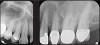

There are two specific types of DIDR sensor systems available to dentists in the marketplace: the hard-wired (HW) sensor and the photostimulable phosphor (PSP) sensor,1,2 also commonly known as phosphor "plates." A desirable feature common to both modalities is the ability to expose either bitewing (BW) or PA radiographic images. The BW radiograph (Figure 1) is usually considered more appropriate for caries detection, whereas the PA (Figure 2) is diagnostic for several different anatomic and pathologic issues.7

Fig 1. Left: Representative PSP BW radiograph with multiple restorative materials of varying radiographic densities. Tooth No. 31 demonstrates deep

caries on mesial aspect beneath the restorative. Radiolucency of carious lesion results from the low relative density of caries compared with healthy

tooth structure. Right: PSP BW radiograph optimized for view of multiple interproximal carious lesions.

Figure 1